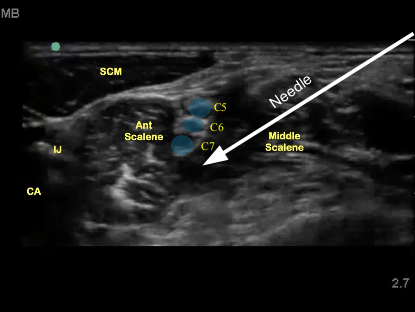

In the POCUS space, we have specialized in many different modalities including artificial intelligence, ultrasound-guided nerve blocks as well as bowel ultrasound. Specifically, investigators have both state and federal NIH funding to develop algorithms alongside clinical engineers.

Lahey Clinic is the home of the Ultrasound-Guided Nerve Block (UGNB) repository assisting investigators determine the efficacy and safety of UGNB's nationally.